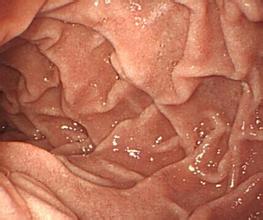

乌兰察布恒大医院胃肠医生介绍:萎缩性胃炎是消化系统常见病之一,在我国人群中,慢性胃炎发病率高,慢性萎缩性胃炎多由浅表性胃炎不治疗转化而成。

萎缩性胃炎的病因是什么?